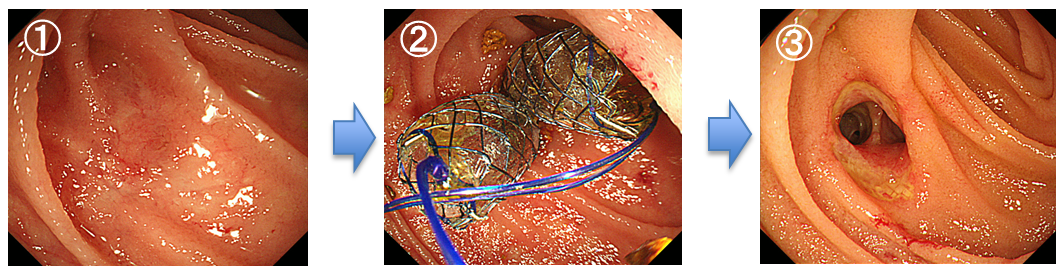

比較的大きな十二指腸乳頭部腺腫に対して、内視鏡的乳頭部切除を施行しました。病理組織診断では十二指腸乳頭部癌(腺腫内癌)でした。切除断端は陰性で完全切除が得られており、追加治療を行うことなく経過観察となりました。その後も再発は認めていません。

内視鏡的乳頭切除術

左上:十二指腸乳頭部に認めた腫瘍性病変。

右上:スネアを用いて病変を一括切除。

左下:切除後の乳頭部の所見。

右下:切除標本。病理組織診断にて十二指腸乳頭部癌(腺腫内癌)と診断され完全切除となった。